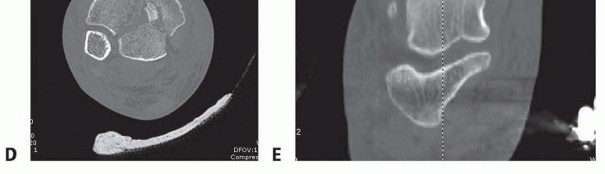

Radiographs of the knee and ankle are necessary to evaluate any articular fracture involvement or associated knee or ankle subluxation or dislocation. Identifying any occult fracture lines aids in the preoperative planning of potential pin placement. Many patients with high-energy tibial fractures have associated foot injuries, and views of the foot and ankle are necessary to identify this injury pattern. Traction radiographs of articular injuries of the tibia are useful to identify the nature and orientation of metaphyseal fragments as well as degree of articular impaction. This aids in determining whether a joint-spanning fixator is necessary. Distraction computed tomography (CT) scans should be obtained

after

the knee- or ankle-spanning fixator has been applied. These studies indicate the effectiveness of the ligamentotaxis reduction. This allows the surgeon to determine the preoperative plan for definitive fixation once the soft tissues have recovered 14 ( FIG 5). 535

### FIG 5 •

D,E. CT scan obtained post distraction in the frame provides valuable information to help determine the preoperative plan for delayed definitive reconstruction once the soft tissues have recovered.